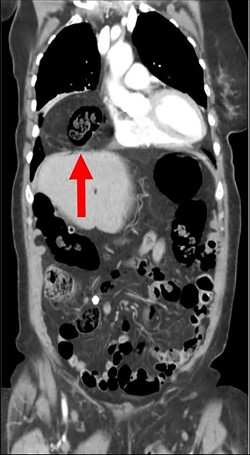

During the hospitalization, initial cardiac workup with 12-lead electrocardiogram and serial troponins was negative. The patient’s oncologic medications were held without improvement of the pain as well as to prevent leukopenia and neutropenia, if surgery was indicated. Palliative care was unable to achieve adequate pain control with oral and IV medications, and the patient did not want to pursue hospice care. Surgical consultation was obtained, and further evaluation with a CT scan of the chest, abdomen and pelvis with oral and IV contrast demonstrated an anteromedial diaphragmatic defect through which a prominent amount of mesenteric fat and a portion of the colon herniated representing a Morgagni hernia (Figs. 1–4). An increase in the size of the previously known PEH as well as the Morgagni hernia was noted. Due to continued chest pain unrelieved by opioids, a joint decision was made between surgeon, oncologist and the patient to proceed with surgery. She underwent successful robotic laparoscopic repair of the Morgagni hernia and PEH with dulex mesh for reinforcement. Her chest pain subsequently resolved. The patient gradually tolerated oral feeds and was eventually discharged in stable condition.

A CT chest, abdomen and pelvis with PO and IV contrast in 2017 shows bowel gas with mesentery herniating anteriorly through a diaphragmatic defect, consistent with a Morgagni hernia (red arrow) that has increased in size since 2015.